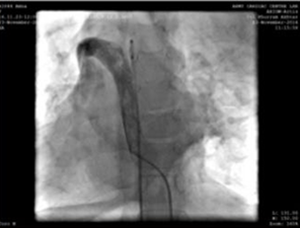

Nadi femoral dan arteri kanan diberi selubung radial 5F. Selama prosedur, kami menemukan vena cava (IVC) inferior untuk mengeringkan kelanjutan azygous menuju vena cava superior kanan dan kemudian Lacak melalui sinus koroner yang dildo di atrium kanan. Sebuah keputusan untuk menjalankan prosedur dari pembuluh darah internal kiri (dengan diakses 5F radial) dibuat.

Tusukan pembuluh darah jugler kiri, dan kateter angiografi 5F, menunjukkan pembuluh lengan atas-jalur koneksi atrium kanan vena cava superior.

Kami menggunakan selubung pengiriman 9F, yang canggih dan ditempatkan di aorta turun di atas guidewire super kaku. MemoPartTM cone shape PDA occluder 14/12 mm, was attached to the delivery cable and progressed across the delivery sheath. The placement of the occlude was proper with no residual flow.